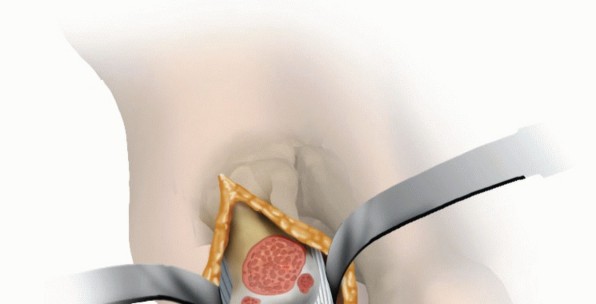

20. Surgical Management

Central defect in articular cartilage noted with unstable cartilage (TECH FIG 7A)

21. TECH FIG 7 • A. Central chondral defect. B. Central chondral defect débrided to stable cartilage rim.

(continued)

Débridement of unstable cartilage to stable residual cartilage rim (TECH FIG 7B). Microfracture (TECH FIG 7C)

In this case, central defect filled with commercially available allograft cartilage (TECH FIG 7D,E) Contains extracellular matrix, including type II collagen, proteoglycans, and growth factors

Fibrin glue to seal the defect and contain the extracellular matrix (TECH FIG 7F,G) Postoperative Care

22. TECH FIG 7 • (continued) C. Microfracture for central defect, performed with a small joint microfracture awl.

23. D. Central chondral defect being filled with commercially available allograft cartilage. E. Allograft cartilage filled to match the native first metatarsal head cartilage. F. Fibrin glue to seal the allograft cartilage within the defect. G. Appearance immediately prior to closure. No shear by first proximal phalanx on filled first metatarsal head defect.